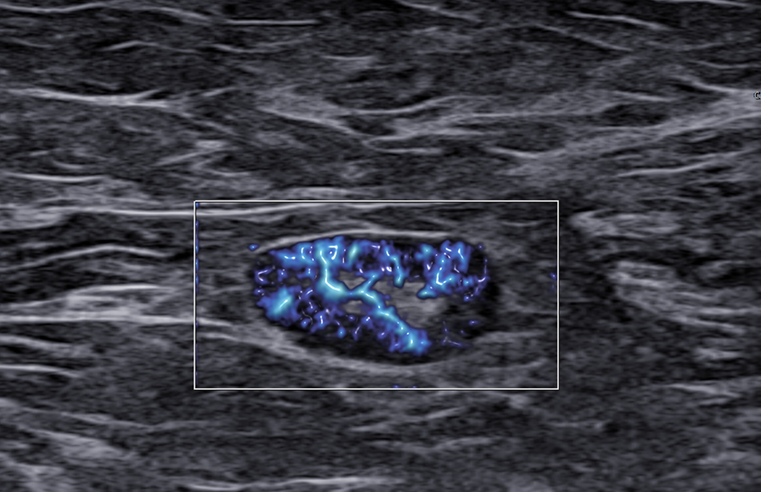

Rak piersi a obraz węzłów chłonnych. LN-RADS - część 2